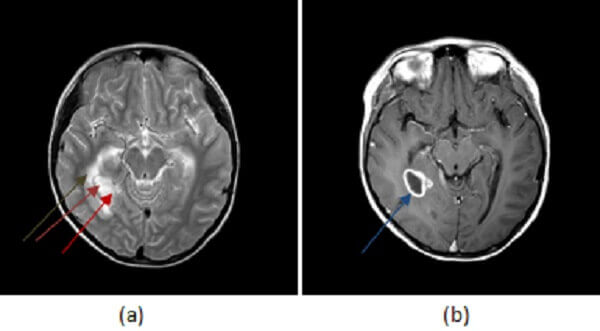

Figure 1: (a) right medial temporal lobe mass has high T2 signal centrally (red arrow) and a low T2 rim (purple arrow). There is surrounding vasogenic edema (brown arrow). (b, blue arrow) T1 post contrast demonstrates thick walled rim enhancement . There is also central restricted diffusion (green arrow, ADC not shown but low signal).

Most brain abscesses result from hematological dissemination of infection; as a result, the grey white junction (site of greatest blood flow) is the most common location. Early infection of the brain parenchyma is termed cerebritis and is characterized by a focal infiltration of inflammatory infiltrates, manifested on MRI by T2/FLAIR hyperintensity without restricted diffusion or enhancement. If left untreated, cerebritis may mature into an abscess – a mass with central necrosis contained by a rim of fibroblasts, manifested by central restricted diffusion with an enhancing, sometimes hypointense T2 rim and extensive vasogenic edema. Smaller “daughter” abscesses may also be present. These characteristics, unique to the pathology of abscesses, help distinguish them from other causes of rim enhancing brain masses.